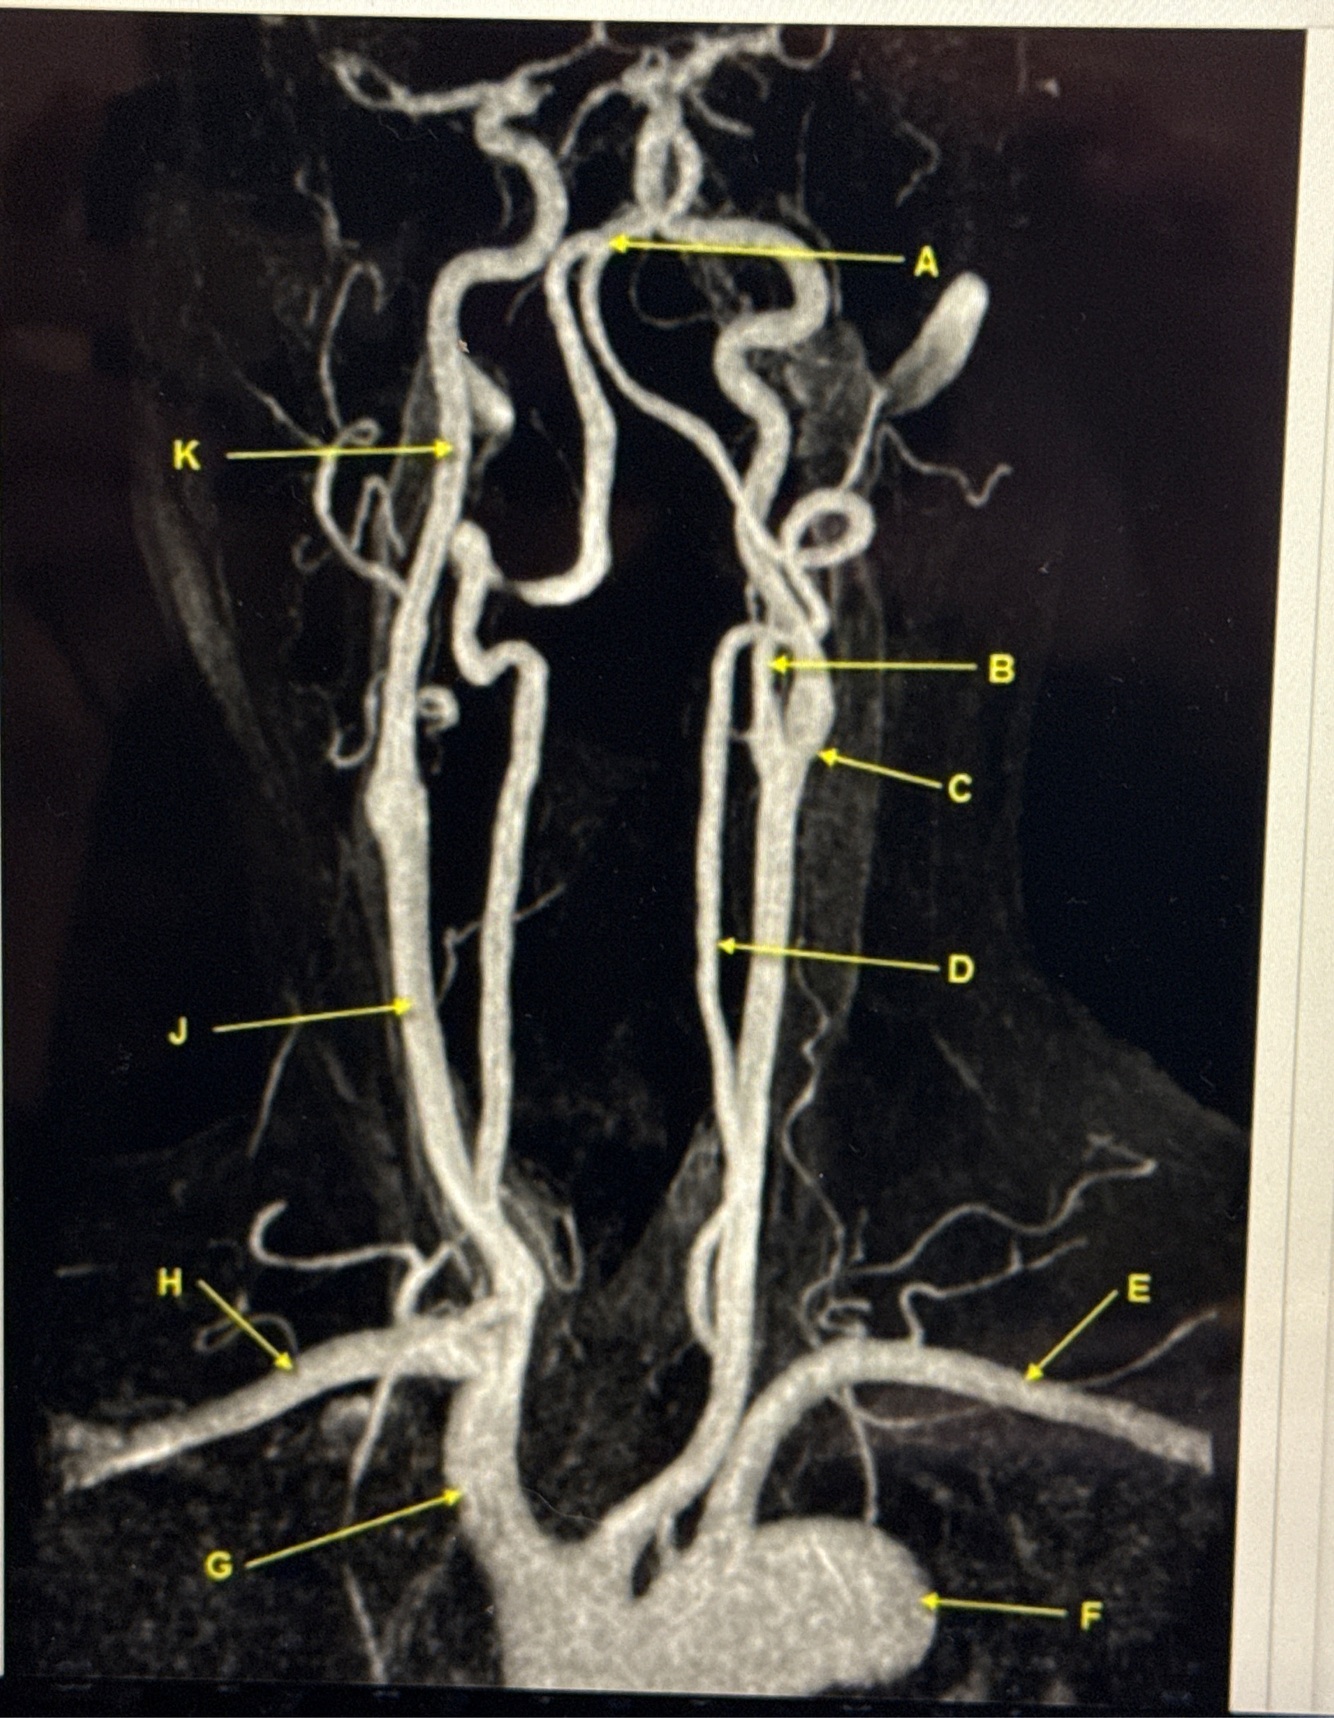

Q

What kind of MR image

A

MRA EXTRACRANIAL CIRCULATION

9

Letter B points to

10

Letter J points to

11

Letter A points to the

12

Letter E points to the

13

Letter K points to the

14

Letter C points to the

16

VertebroBasilar junction

17

Letter B points to the _______ and letter D points to the ______

B. External carotid artery

D. Vertebral artery

18

19

Letter E points to the _____ and letter F points to the _____

E. Left subclavian artery

F. Thoracic aorta

20

Letter G points to the _____ , letter H points to ______ and letter J points to the

G. Brachiocephalic

H. Right subclavian artery

J. Common carotid artery

21

22

Letter K points to the ________,

K. Internal carotid artery